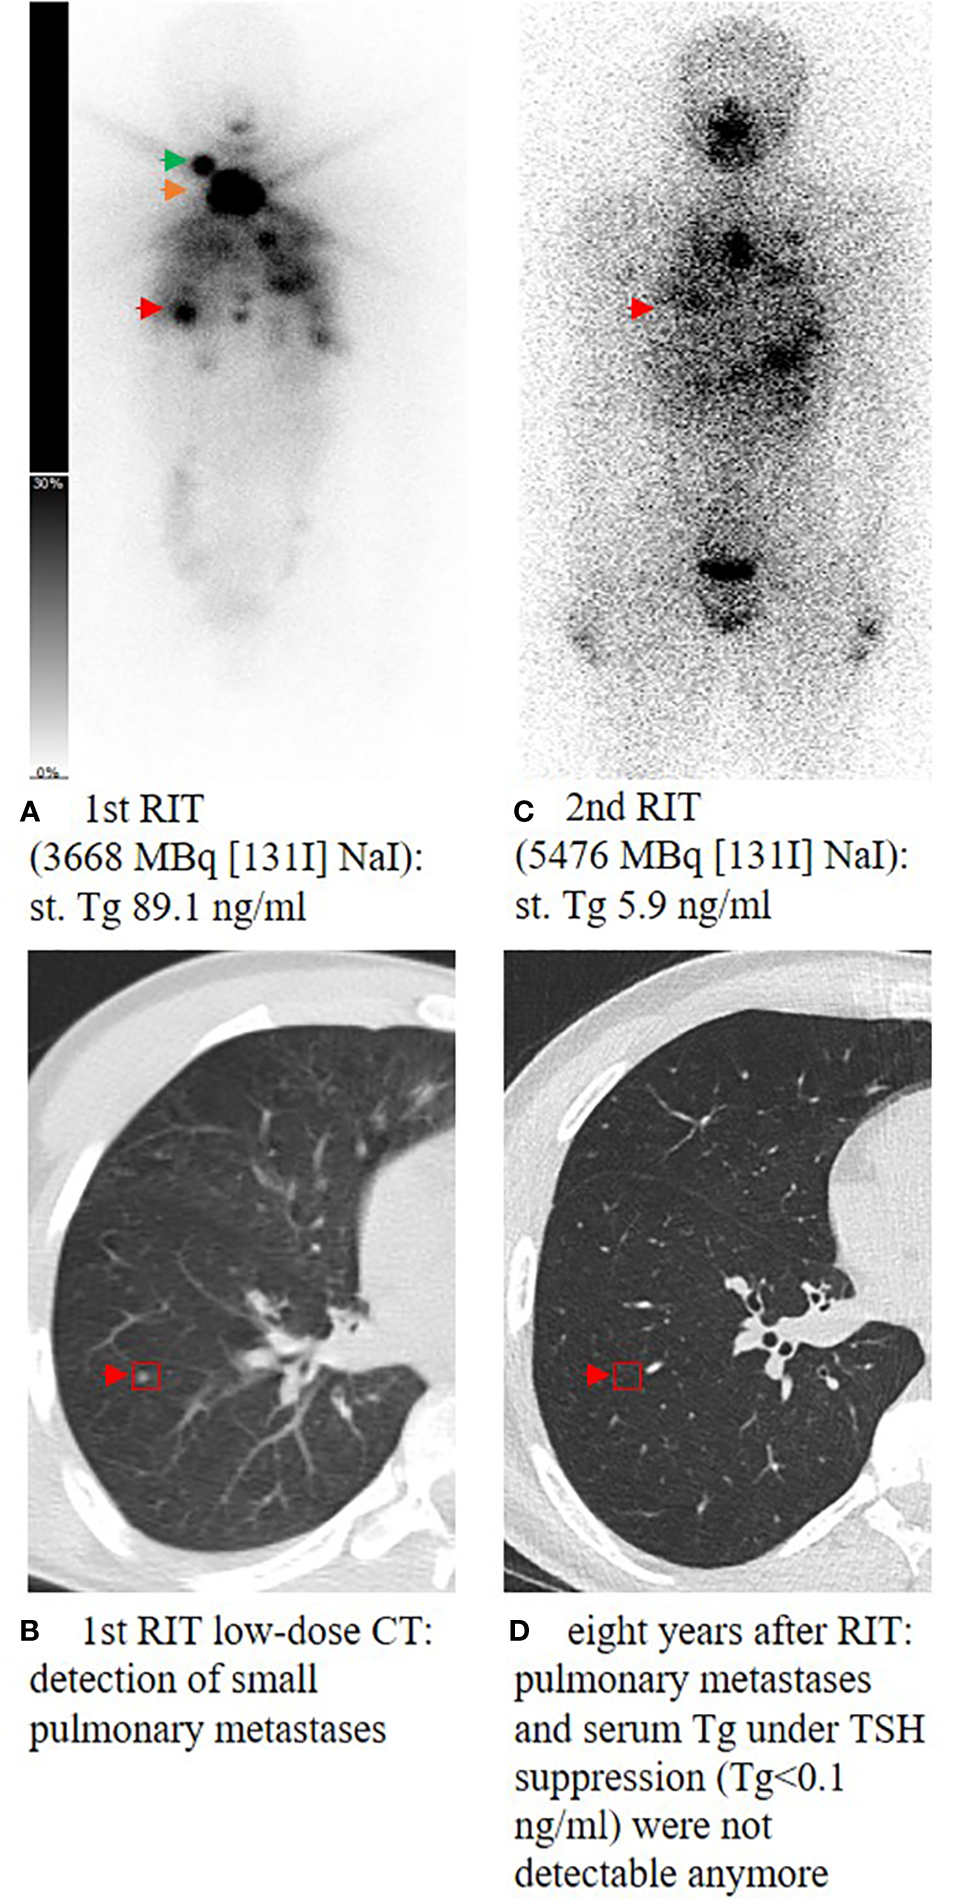

Figure 1

Planar whole-body scintigraphy and CT scan after the first radioiodine therapy (RIT) and during follow-up. A 14-year-old male patient (A) presenting with high residual thyroid bed uptake (orange arrow), an iodine-positive cervical lymph node metastasis in level II on the right side (green arrow), and multiple iodine-positive pulmonary metastases (red arrow) (B). Post-therapeutic scan of the second RIT showed ablation of the remnant thyroid tissue and significant uptake of pulmonary metastases (C). During follow-up, TSH was suppressed consequently; 1.6 years after the last RIT, Tg decreased to <0.1 ng/mL and pulmonary metastases could not be detected anymore in the subsequent CT scans (D). At the last visit, 8 years after the first RIT, the patient still presented with excellent response with Tg <0.1 ng/mL and no remarkable findings in computer tomography of the lung. st., stimulated; Tg, thyroglobulin; RIT, radioiodine therapy; TSH, thyroid-stimulating hormone.

At the time of surgery, 20 patients were prepubertal and 65 patients were pubertal/postpubertal. Tumor-node-metastasis (TNM) classification is presented in Table 3. Notably, prepubertal patients presented with significantly higher T and M stages. Furthermore, prepubertal patients presented more often with extrathyroidal extension and were diagnosed more often with R1 and N1 stage without reaching statistical significance (p-value 0.196, 0.109, and 0.102, respectively). RIT with an initial dose of 3,584 ± 1,254 MBq [131I] NaI (96 ± 34 mCi) was performed within a median of 36 days (14; 177 days) after surgery. At the time of the first RIT, distant metastases were unknown. The first RIT was performed with the aim of either remnant ablation in four prepubertal patients (20%) or adjuvant therapy in 16 prepubertal patients (80%) and either remnant ablation in 19 pubertal/postpubertal patients (29%) or adjuvant therapy in 46 pubertal/postpubertal patients (71%; p = 0.568). In the post-therapy [131I] NaI scan, cervical lymph node metastases were detected in 8/85 patients (4/20 prepubertal; 4/65 pubertal/postpubertal). Radioiodine-positive distant metastases were diagnosed in six patients (7%; 2/20 prepubertal; 4/65 pubertal/postpubertal; Figure 1).